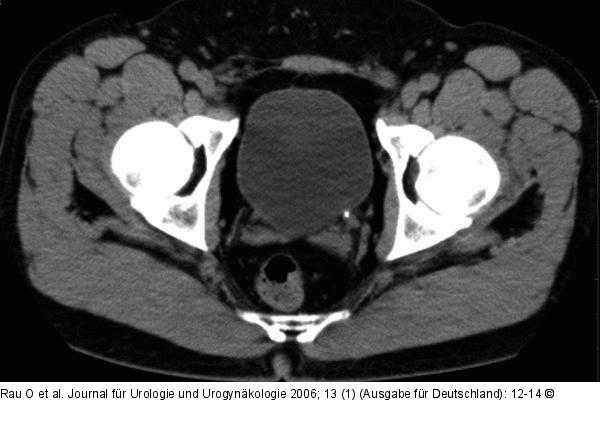

Abbildung 1: Harnleiterstein Unmittelbar prävesikal gelegener distaler Harnleiterstein links. Natives Spiral-CT. |

Abbildung 1: Harnleiterstein

Unmittelbar prävesikal gelegener distaler Harnleiterstein links. Natives Spiral-CT. |